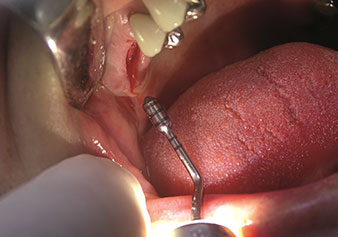

W&H bietet auch die perfekte Lösung für den internen Sinuslift an Nach der Kieferhöhlenpräparation mit dem

entsprechenden Instrumentarium (Abb. 3) erfolgt mit dem neuen Instrument Z35P (Abb. 4) die hydrodynamische Abhebung der Membran. Mit dem gleichen Instrumentenset kann auch die Implantatbett-Aufbereitung piezochirurgisch in aufsteigenden Durchmessern erfolgen (Abbildung drei und vier mit freundlicher Genehmigung von Dr. Mario Kirste, Frankfurt/Oder).

Implantatbettaufbereitung mit Instrument I4P

Abb. 3: Implantatbettaufbereitung mit Instrument I4P. Foto: © Dr. Mario Kirste (Frankfurt / Oder)